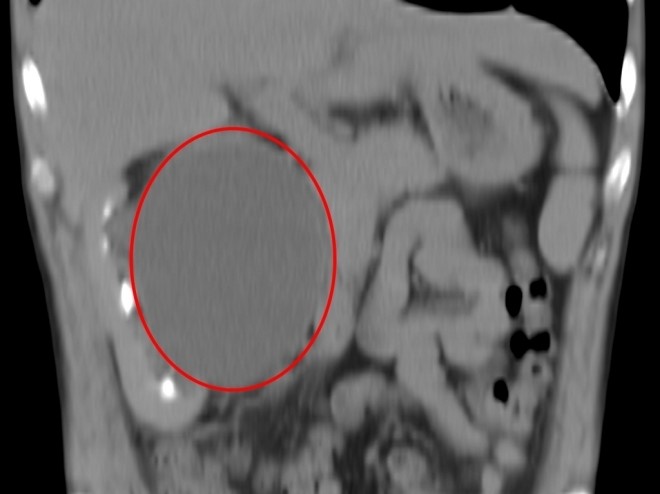

- Патологией кисты почек принято считать ее аномальное увеличение в размерах. Медицине известны случаи, когда паренхиматозная киста достигала 10 и более сантиметров в диаметре. Паренхиматозная киста левой почки что это такое, когда опухоль увеличивается? При таких размерах киста гарантированно нарушает работу внутренних органов, приводит к воспалениям и инфекционным заболеваниям органов брюшной полости.

- Паренхиматозная опухоль больших размеров провоцирует тупые и тянущие боли в нижней части живота, которые вызваны преимущественно тем, что разросшаяся киста начинает придавливать и угнетать соседние органы брюшной полости, ухудшать их функционирование.

Наиболее явным признаком появления кисты большой величины является увеличение ее в размерах и возможность методом пальпации определить место поражения. Особенно большие поликистозные опухоли видны невооруженным взглядом, если больной не имеет лишнего веса.